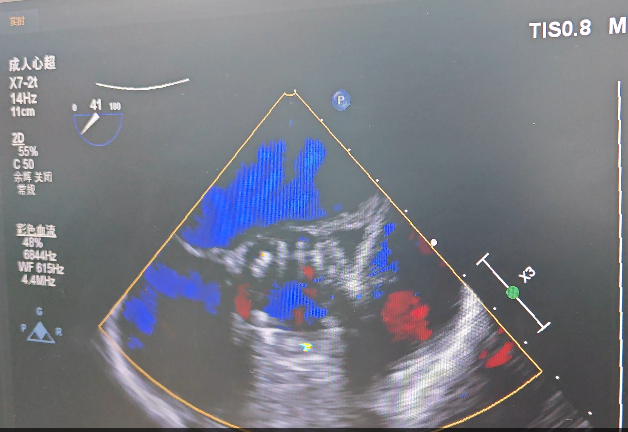

患者因“反复胸痛1月、伴晕厥1次”入住腾冲市中医医院心血管病科,进一步完善心脏彩超检查。心脏彩超提示:1.主动脉重度狭窄伴轻度关闭不全,致左房内径增大、左室壁明显增厚;2.二尖瓣轻度关闭不全;3.三尖瓣轻度关闭不全。诊断为主动脉瓣重度狭窄并关闭不全,心功能Ⅱ-Ⅲ级。经请上级医院专家会诊讨论,患者年龄大,心功能较差,符合TAVR手术绝对适应症,可以进行经导管主动脉瓣置换术(TAVR)治疗。

超声查看无瓣周漏

术后经导管测压显示,跨瓣压差由术前的62mmHg降低为8.75mmHg,血流动力学极大改善,超声提示人工瓣膜工作状态良好、微量瓣周漏。